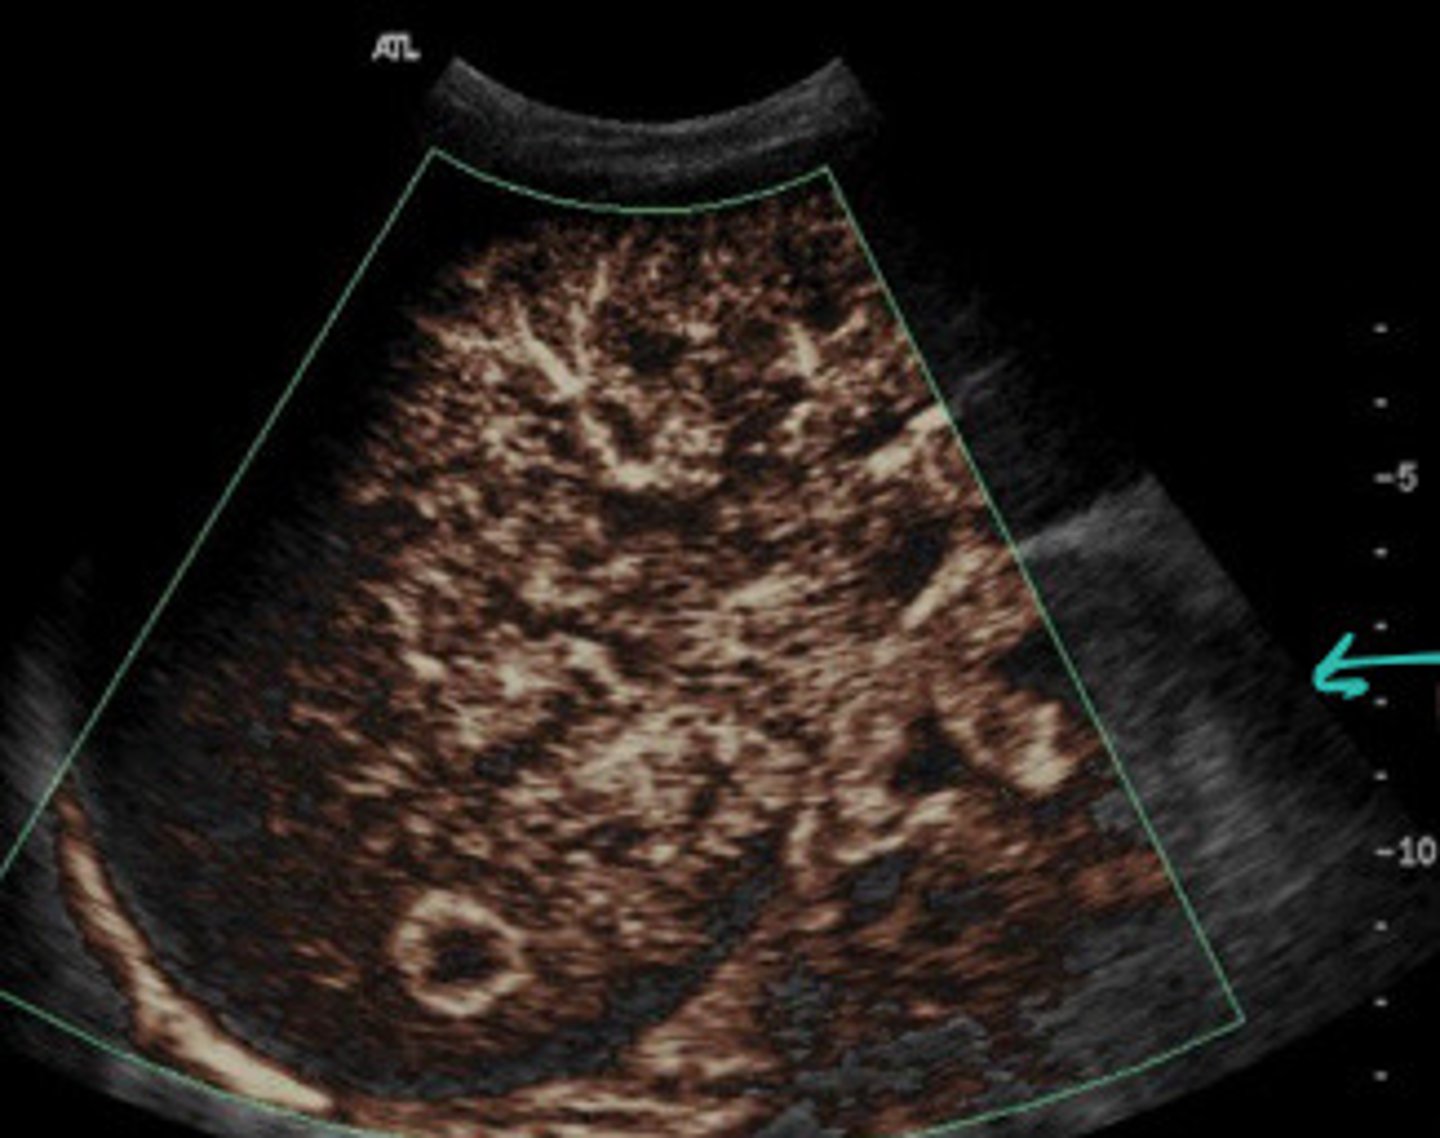

What does this image show

FNH (seen better with colour map)

FNH

What are the arrows pointing to